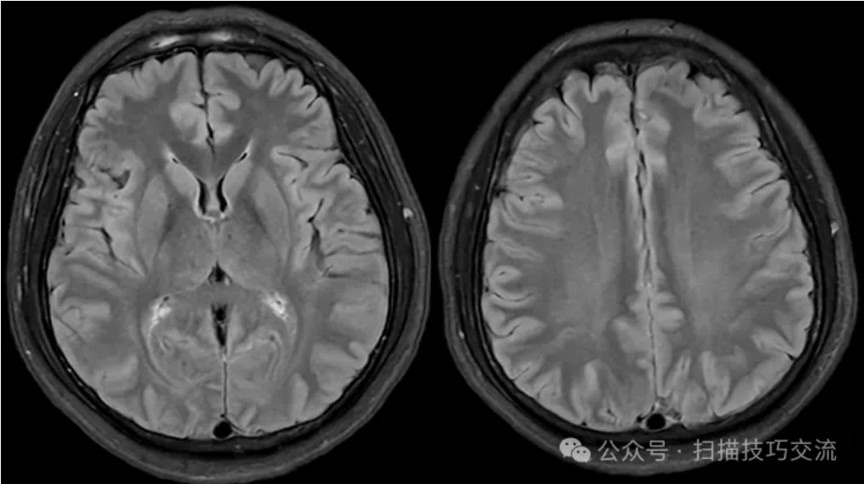

•汗腺分泌:正常,皮肤划痕正常反应。 •尿便障碍:无。性功能障碍无。 •专科情况:正常。不逐一罗列。 •辅助检查:01-05颅脑CT提示:1,上矢状窦、双侧横窦密度较高,请结合临床,必要时进一步检查;2,双侧脑室后角可疑稍高密度影,右顶叶局部脑沟密度可疑增高,建议进一步检查。 •初步诊断:静脉窦血栓

临床申请:颅脑平扫,静脉成像,磁敏感成像,颅内静脉血管黑血成像。

图像不逐一罗列,未见异常。